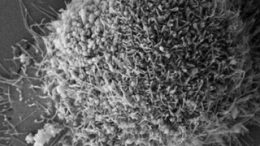

Ερευνητές στη Βρετανία -μεταξύ των οποίων τρεις Έλληνες επιστήμονες- ανακάλυψαν…